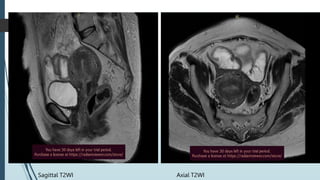

Sagittal T2WI Axial T2WI

Coronal T2WI Coronal T2 STIR

 Uterus is bulky with diffuse junctional wall widening upto 13 mm

 Uterus shows homogenous post contrast enhancement. No

diffusion restriction seen in that widened junctional zone.